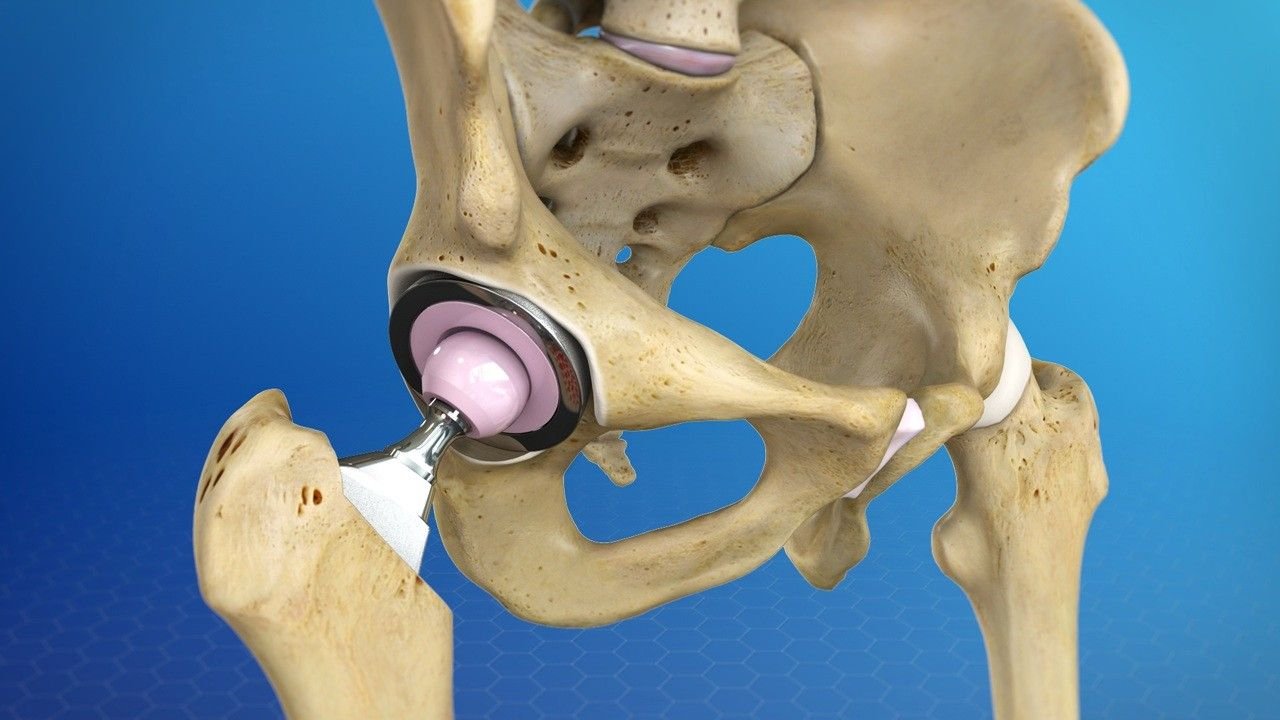

Hip Replacement, also known as hip arthroplasty, is a surgical procedure where the damaged or worn-out parts of the hip joint are replaced with artificial implants. It is recommended for patients suffering from severe hip pain, stiffness, and restricted mobility caused by conditions like osteoarthritis, rheumatoid arthritis, fractures, or degenerative joint diseases.

Persistent hip pain affecting daily activities

Limited mobility and difficulty walking or standing

Joint stiffness unresponsive to medications or physiotherapy

Hip fractures or severe joint damage

Poor quality of life due to chronic discomfort